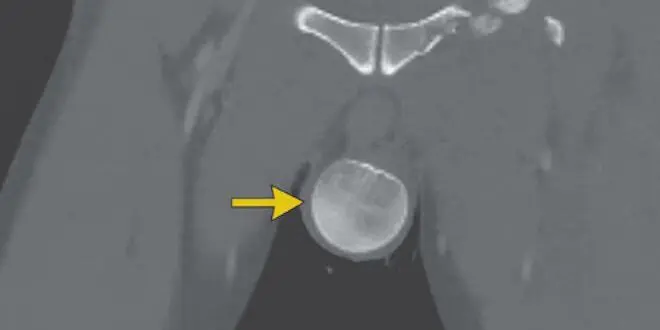

Un scanner du bassin a confirmé une luxation de la hanche gauche, ainsi qu'une fragmentation en trois segments du fémur gauche. Quant à la tête et au cou du fémur, ceux-ci étaient désormais dans le scrotum.